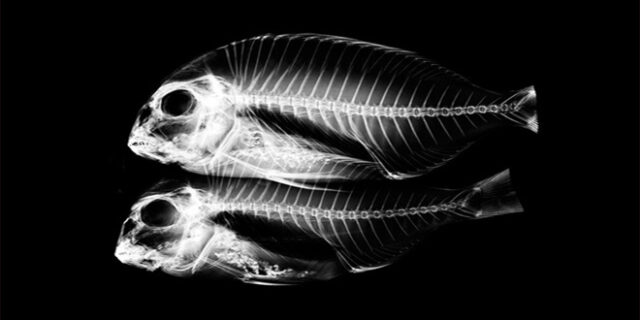

GE, Wilhelm Röntgen’in X ışınlarını keşfettiği gün olan 8 Kasım Uluslararası Radyoloji Günü’nü (IDoR), SeeInsideIT adlı bir kampanya ile kutladı.

Plastik ördekten, arı kovanına; elektro gitardan eski oyun konsoluna kadar dikkat çekici 50’den fazla nesneye ait radyolojik görüntülerin tüm dünya ile paylaşılacağı kampanya ile günümüzde radyolojinin sağlık hizmetlerinde sahip olduğu rolün öneminin ortaya konulması hedefleniyor.

Bilgisayarlı Tomografi – CT , Manyetik Rezonans – MR